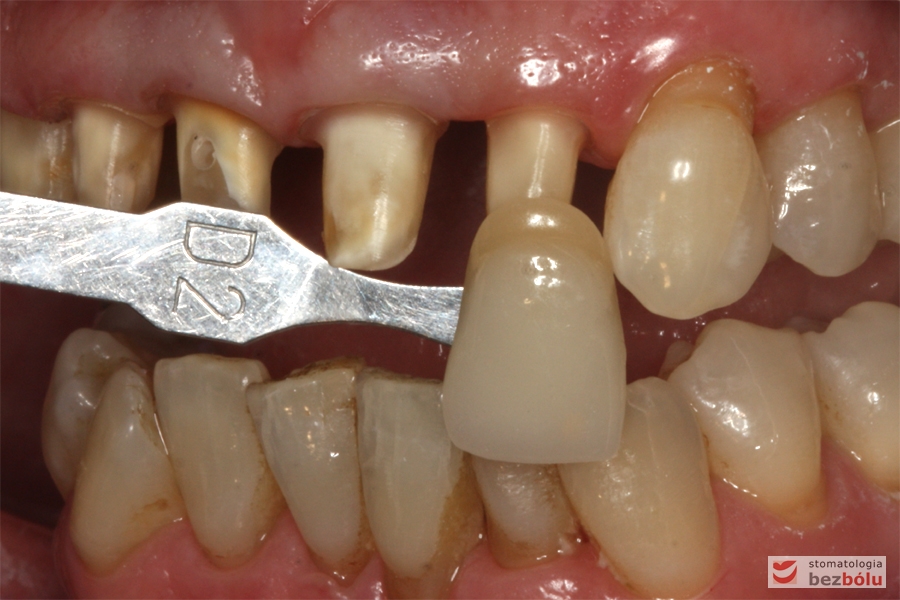

Dobór koloru dla nowych zębów - dobór koloru w odniesieniu do górnego kła po lewej stronie

Dobór koloru dla nowych zębów – dobór koloru w odniesieniu do górnego kła po lewej stronie